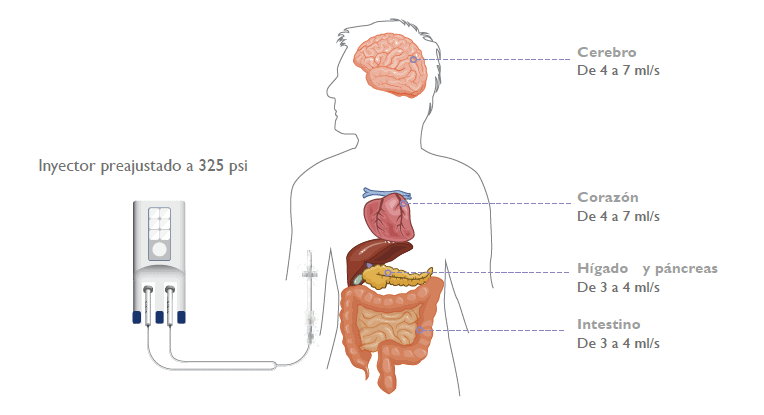

Para poder ver mejor un órgano se puede recurrir a pruebas diagnósticas específicas (mencionadas anteriormente) durante las cuales se va a inyectar un contraste al paciente. El objetivo es “tintar” el órgano diana y poder ver de esta manera su forma, su tamaño o su vascularización.

Este producto de contraste se inyecta con alta presión: es necesario poder administrarlo a gran velocidad. Mediante un inyector que genera una presión muy alta se consigue entonces un alto flujo. El alto flujo del contraste al salir del inyector no es el mismo al entrar en la vena: se ve reducido por el prolongador que conecta el inyector al acceso vascular y la longitud del catéter.

Para poder conseguir las imágenes adecuadas se requiere, en adultos, flujos de entre 3 y 7ml/s, según el órgano que se quiera explorar. Los flujos que alcanzar dependen también del tipo de paciente (niño o adulto):

Actualmente, los reservorios, los catéteres Hickman, los PICCs, los catéteres centrales, los midlines y los catéteres cortos pueden venir con la característica “compatible con la alta presión” (llamada también CT rated o Power Injectable). Sin embargo, es fundamental comprobar siempre que nivel de alta presión y de alto flujo permiten para asegurarse que sean adecuados para la prueba que se quiera llevar a cabo.